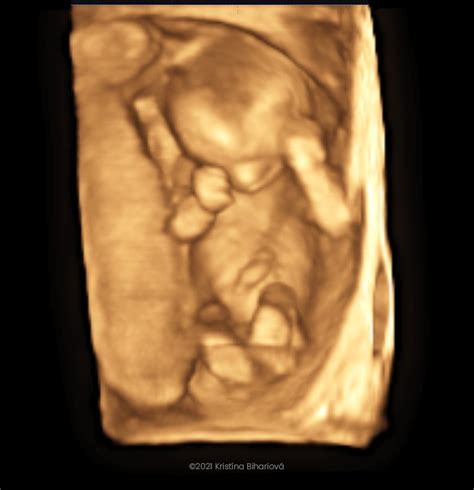

3D ultrazvuk poskytuje trojrozmerné obrazy dieťaťa, zatiaľ čo 4D ultrazvuk pridáva pohyb v reálnom čase. Toto vyšetrenie je trojrozmerné zobrazenie bábätka, z ktorého vám lekár zvyčajne natočí video, na ktorom vidíte aj pohyb dieťatka v reálnom čase. Môžete vidieť, aké má vaše bábätko črty, či dokonca na koho sa podobá. Samozrejme, toto vyšetrenie má svoje limity, nie vždy je úplne zreteľné a vydarené, ale medzi budúcimi mamami je pomerne obľúbené. Lekár vám môže aj vytlačiť 3D fotografiu dieťatka. Tieto vyšetrenia si ale spravidla tehotné ženy hradia.